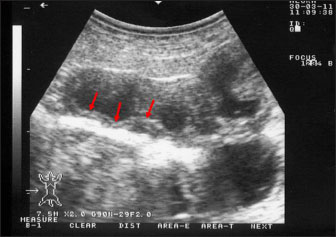

Ultrasonography has been proven effective for the early detection of several abdominal and thoracic disorders in small ruminants (Tharwat et al., 2012b; Tharwat and Al-Sobayil, 2017; Tharwat, 2021; Sadan et al., 2023; Tharwat and Al-Hawas, 2024a,b; Tharwat et al., 2024; Tharwat et al., 2025b). Recently, the technique has been found valuable for the diagnosis of various bacterial and parasitic infections in ruminants (Tharwat and Tsuka, 2024). An overall increase in intestinal mucosa thickness was detected in goats with PTB. It was classified as either mild, moderate, or severe (Fig. 2). Corrugation and folding of the intestinal mucosa may be also imaged in goats with PTB (Fig. 3). However, remarkable enlargement of the mesenteric lymph nodes are the most important findings in goats with PTB (Fig. 4). Other sonographic changes included increased hepatic brightness, intestinal edema consolidated lungs, and pleural, peritoneal, and pericardial effusions (Tharwat et al., 2012b).

Fig. 3. Ultrasonography of the corrugated intestinal mucosa in a goat with paratuberculosis. The lesion (red arrows) was best imaged longitudinally